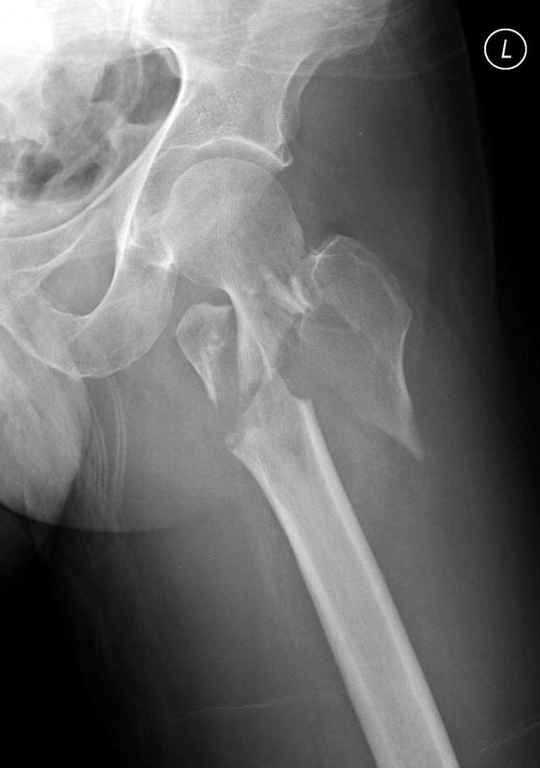

А что тут заставляет сомневаться? Здесь настолько очевидно предпочтителен закрытый интрамедуллярный остеосинтез реконструкционным стержнем (проксимальные гвозди толстоваты для такого молодого возраста), что закрадывается мысь о каком-то подвохе.

Не солидно экономить на пленке, это не делает чести презентации. Такие ограниченные нестандартные снимки приводят к тактическим ошибкам.

Предугадать распространение линий перелома при чрезвертельных и оскольчатых переломах трудно, поэтому для принятия правильного решения рекомендуется Компьютерно Томографические исследование.

При отсутствии КТ, снимок на вытяжении поможет увидеть общую картину расположения отломков, особенно потенциальные места введения импланта. Риск раскола в этом случае огромный, поэтому больной должен быть дообследован.